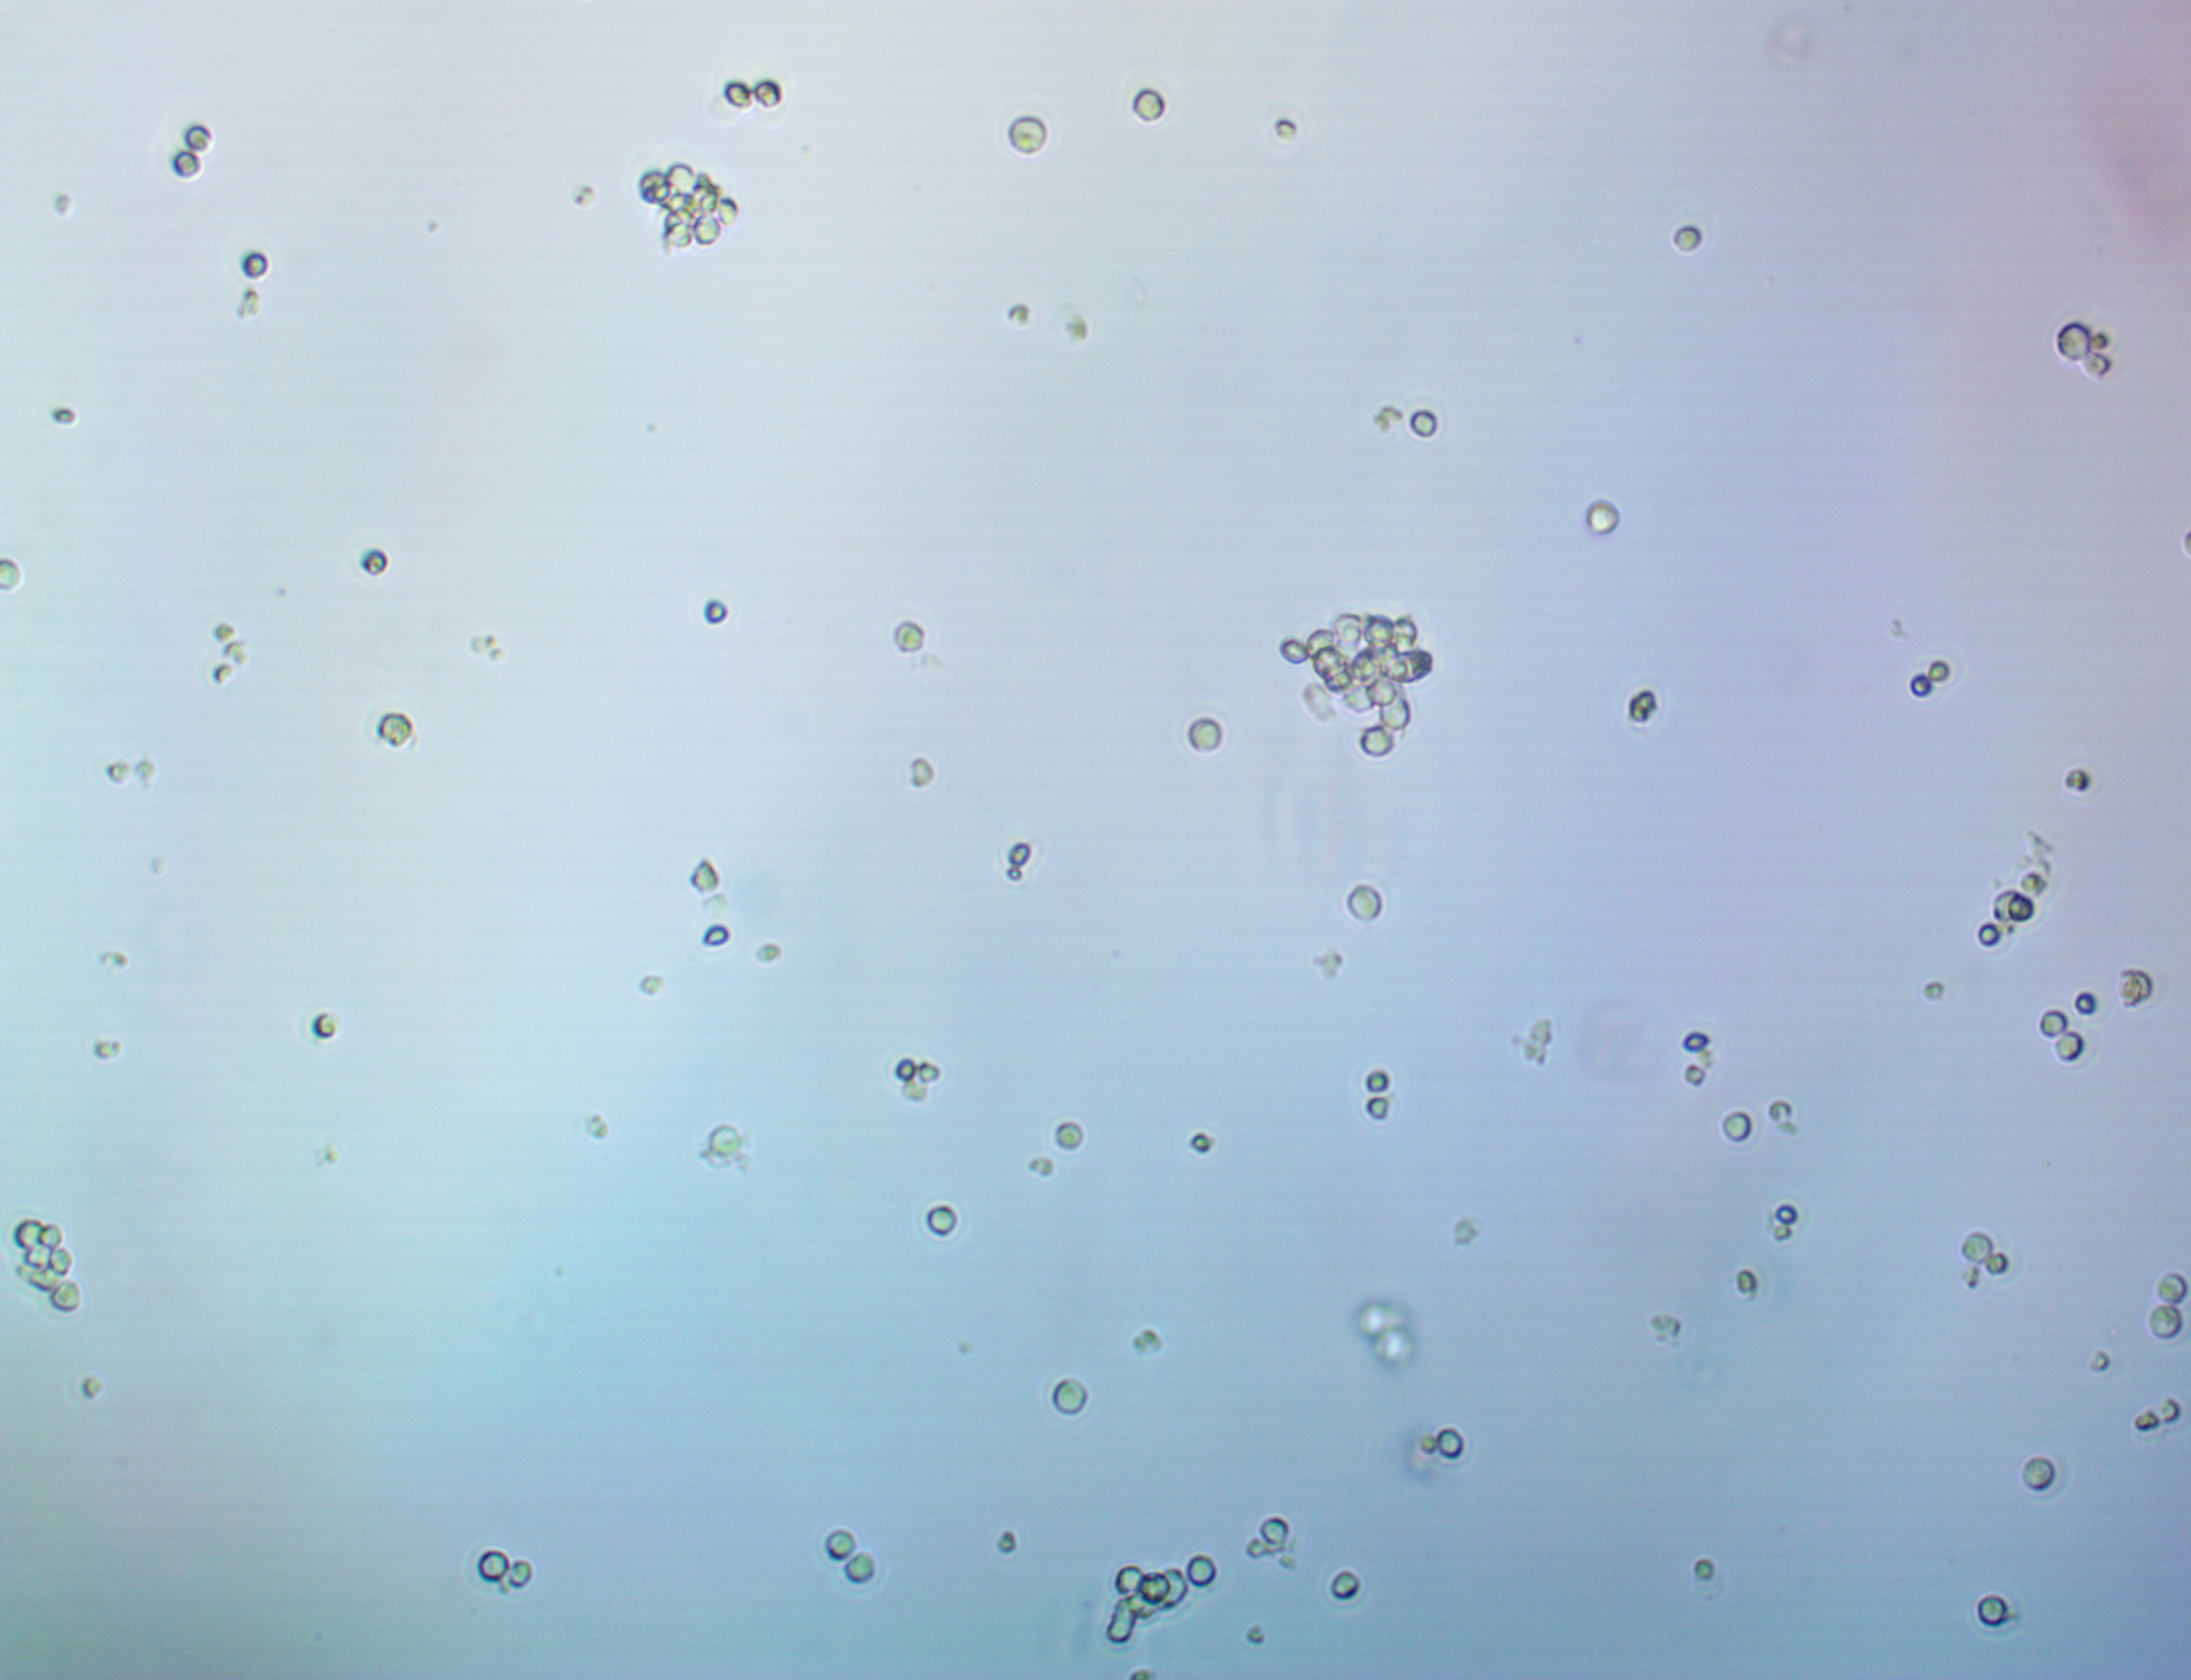

Morphology (suspension): Single or clustered round to oval lymphocytes of small and large size.